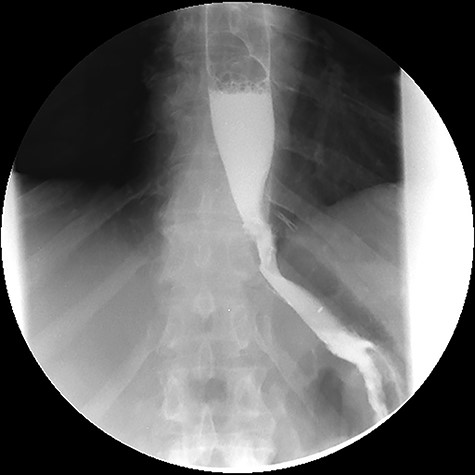

After treatment of the abdominal abscess with percutaneous drainage and antibiotics, an upper GI contrast swallow study confirmed persistency of the GGF without any spillage of contrast to the abdominal cavity (see Fig. 9). The patient was discharged, medicated with oral PPIs.

Upper gastrointestinal contrast swallow study image showing progression of contrast from the oesophagus to the gastric pouch and from the gastric pouch to the excluded stomach, confirming a gastro-gastric fistula.